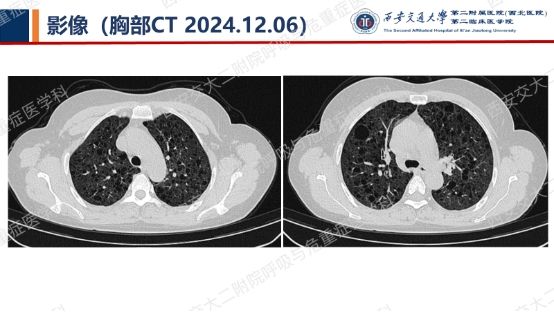

阅影探案,析病寻踪 // 第一期(上)

结合以上患者病史及胸部CT,第一诊断分别考虑???欲知答案,且看后期!!!